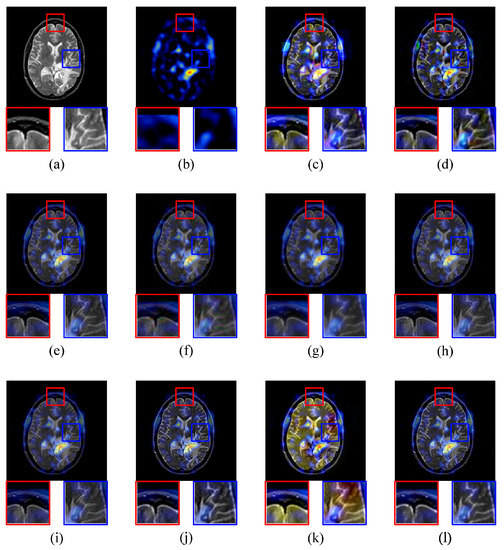

4.2.2. MRI-PET Image Fusion Comparative Experiments

4.2.3. MRI-SPECT Image Fusion Comparative Experiments